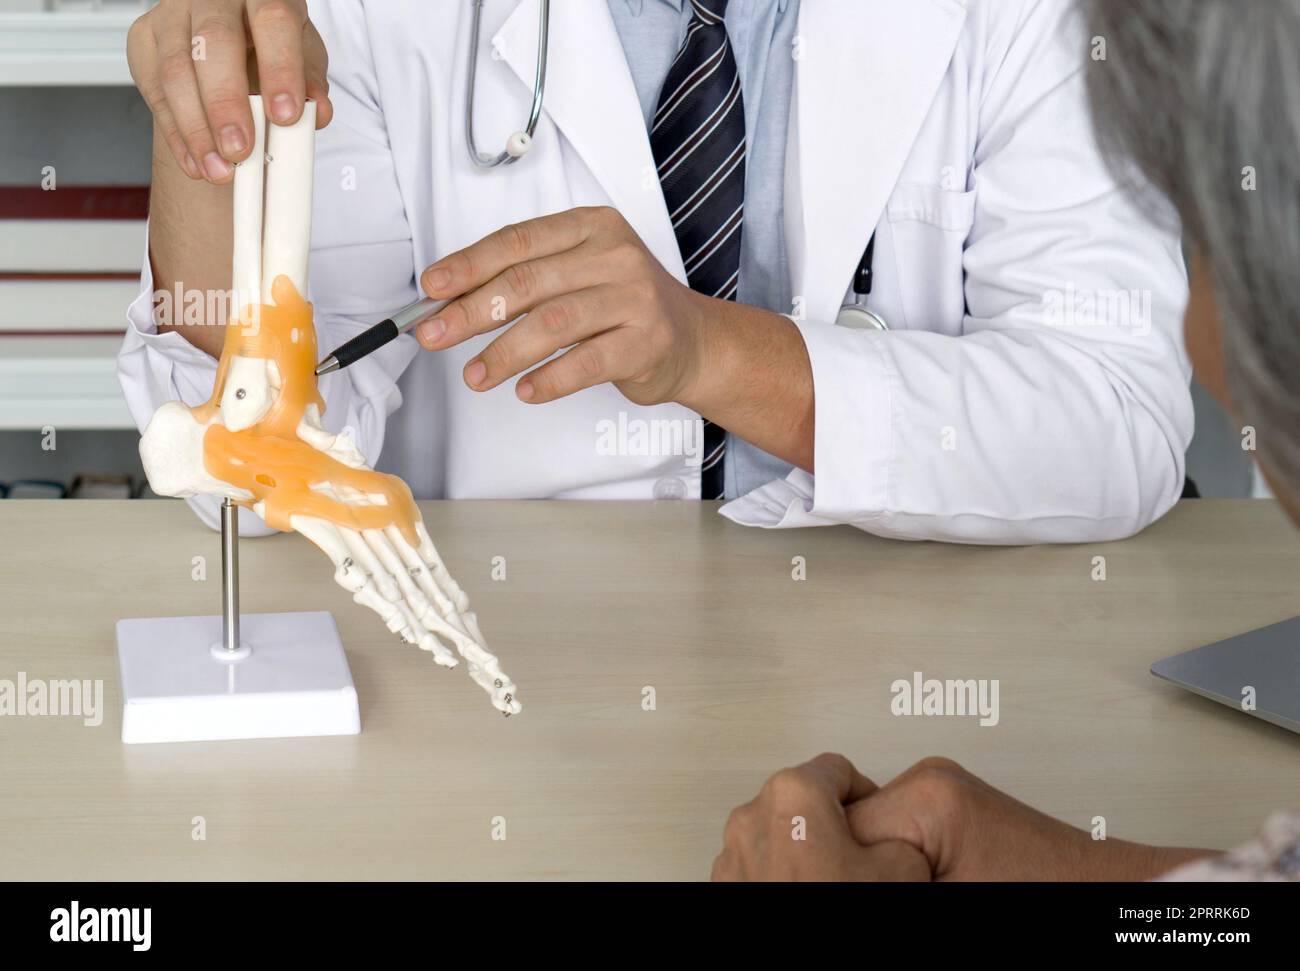

RF2PRRK6D–Chirurgien orthopédique en robe blanche et stéthoscope pointant sur le squelette humain pied cheville os modèle anatomique d'articulation, présenter au patient âgé au sujet du traitement de la cheville avec la chirurgie.